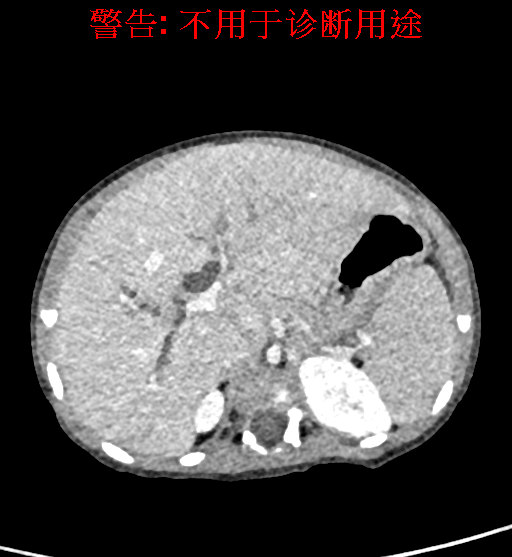

辅助检查: 腹部彩超,上腹部CT 动态增强扫描,考虑胆总管囊肿可能性大。

实验室检查: 血常规:WBC 16.16*109/L,NEU2.88*109/L,RBC3.76 1012/L,HB 92g/L, PLT 414*109/L 生化全套:ALT 50.00 U/L, AST 147.00 U/L, ALT/AST 0.34,LDH 367.00 U/L, ALB 36.91g/L, GGT 1297.00 U/L, ALP 1155.00 U/L, BIL-T 138.23 umol/L, BIT-D 97.01 umol/L, TBA 48.40umol/L,ADA 40.00U/L, PAB 121.40mg/L, BUN 1.98 mmol/L, CREA 17.00 umol/L 肝炎全套: 炎症反应标志物:CRP 7.27mg/l 诊疗过程: CT结果输入海信CAS系统后行3D重建及手术规划后,于2018-5-31全麻下行“胆总管囊肿切除+肝总管空肠吻合术”手术治疗: 术前三维重建及手术方案设计: 将0.625mm双源薄层CT资料的静脉期和动脉期Dicom格式文件导入海信CAS系统。 通过调节窗宽窗位调整CT序号,对肝实质,胆囊,下腔静脉,肿瘤,肝动脉、门静脉及肝静脉等进行三维重建;系统自动计算肝脏体积,肝脏体积为648.3ml,通过术前模拟手术,精准判断手术切除范围,进行精密术前规划及讨论后实施手术。 手术步骤: 麻醉成功后,患儿取平卧位,2.5%碘伏消毒手术区皮肤,铺无菌巾单。取右上腹纵口长约5m,切开皮肤、皮下织组,腹直肌前鞘、腹直肌,后鞘和腹膜。探查见:胆总管3×2cm大小,胆囊管迂曲,长约10cm。 剥离、切除胆囊,游离胆总管,将之横断:①近端即肝总管,剪裁后被吻合用;②远端游离切除囊肿内壁,直至胆总管开口于十二指肠处,冲洗后予以结扎缝扎。距treits韧带20cm处横断空肠:①近端与其远端25cm处的空肠侧壁行端侧双层吻合,吻合口通畅;②远端断端封闭,其侧壁剪开,并经横结肠后提至肝门处,与剪裁的肝总管行端侧双层吻合。缝合修补胆囊床及系膜裂孔,肝门部放置橡胶引流管一根。温盐水冲洗腹腔。检查无活动性出血,清点纱布器械无误,依次缝合腹壁各层。手术顺利,麻醉满意,出血不多,未输血,术后病人先进入麻醉恢复室,苏醒后回病房。手术时术者可开启Hisense CAS系统手势控制功能,对肝脏及胆囊解剖结构进行实时、全方观察、评估,起到术中导航作用。 术后病理: 1. (囊肿壁)囊肿性病变,囊壁部分区域衬覆柱状上皮。 2. 慢性胆囊炎。 3. 送检(肝门)淋巴结查见淋巴结1枚,呈反应性增生。 随访情况: 患儿术后2周恢复良好 术前CT检查:动脉期

静脉期